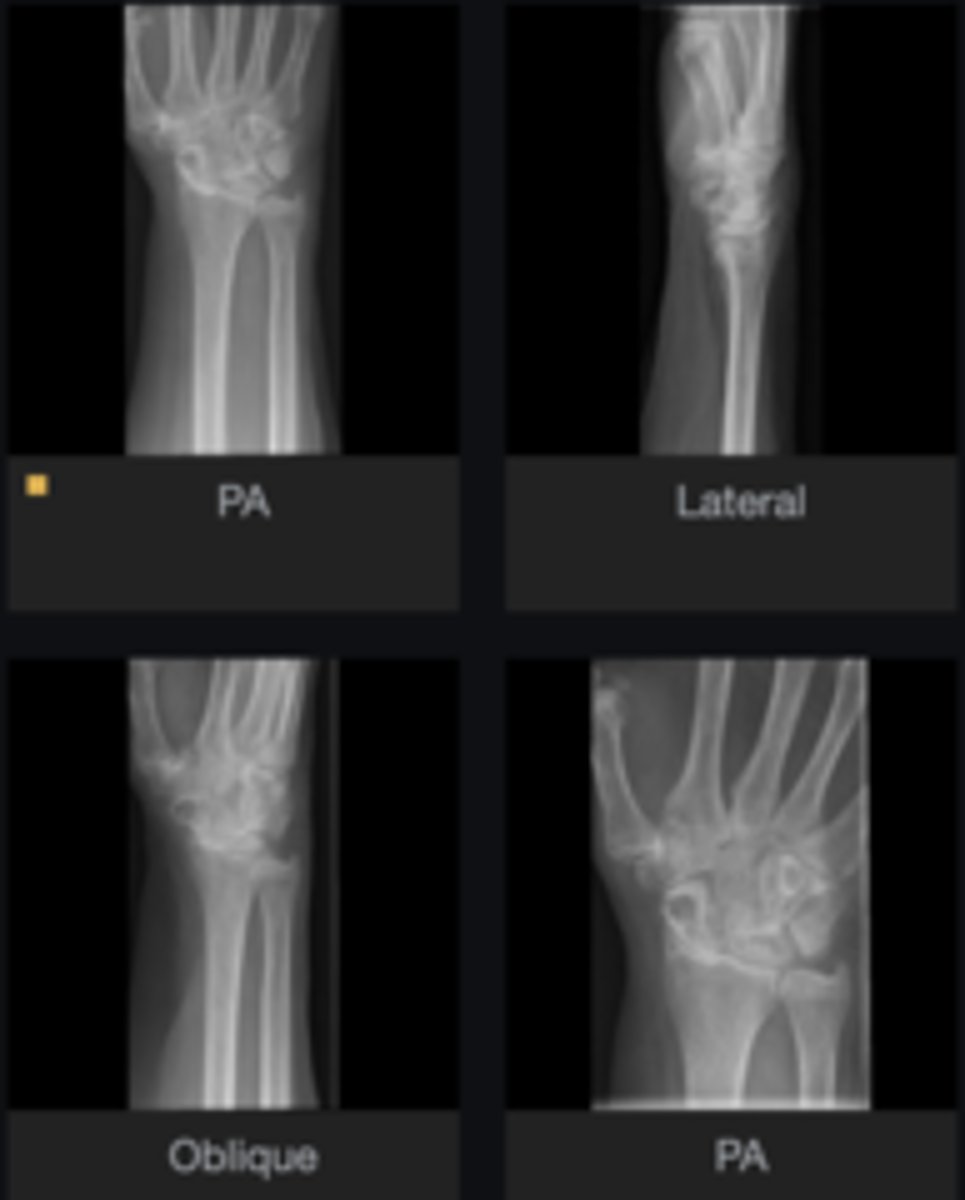

- Sclerosis of scaphoradial junction

- Calcification in triangular fibrocartilage complex

- Loss of joint space

- Subchondral cyst

- Capitate moved proximally

- Scapholunate advanced collapse

List findings

CPPD

Diagnosis?

No

Would you adjust this patient?

Refer to orthopedist

Next step?